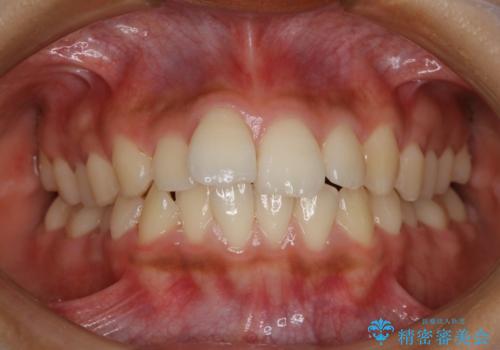

八重歯でがたつきは重度でしたが、きれいな歯並びにすることができました。

がたつきだけでなく、奥歯の噛み合わせのずれの調整もしっかり行いました。

奥歯のずれの調整は時間がかかりますが、矯正後の歯並びの安定度が向上します。

歯並びがきれいになることで、虫歯予防や歯周病予防にもつながります。